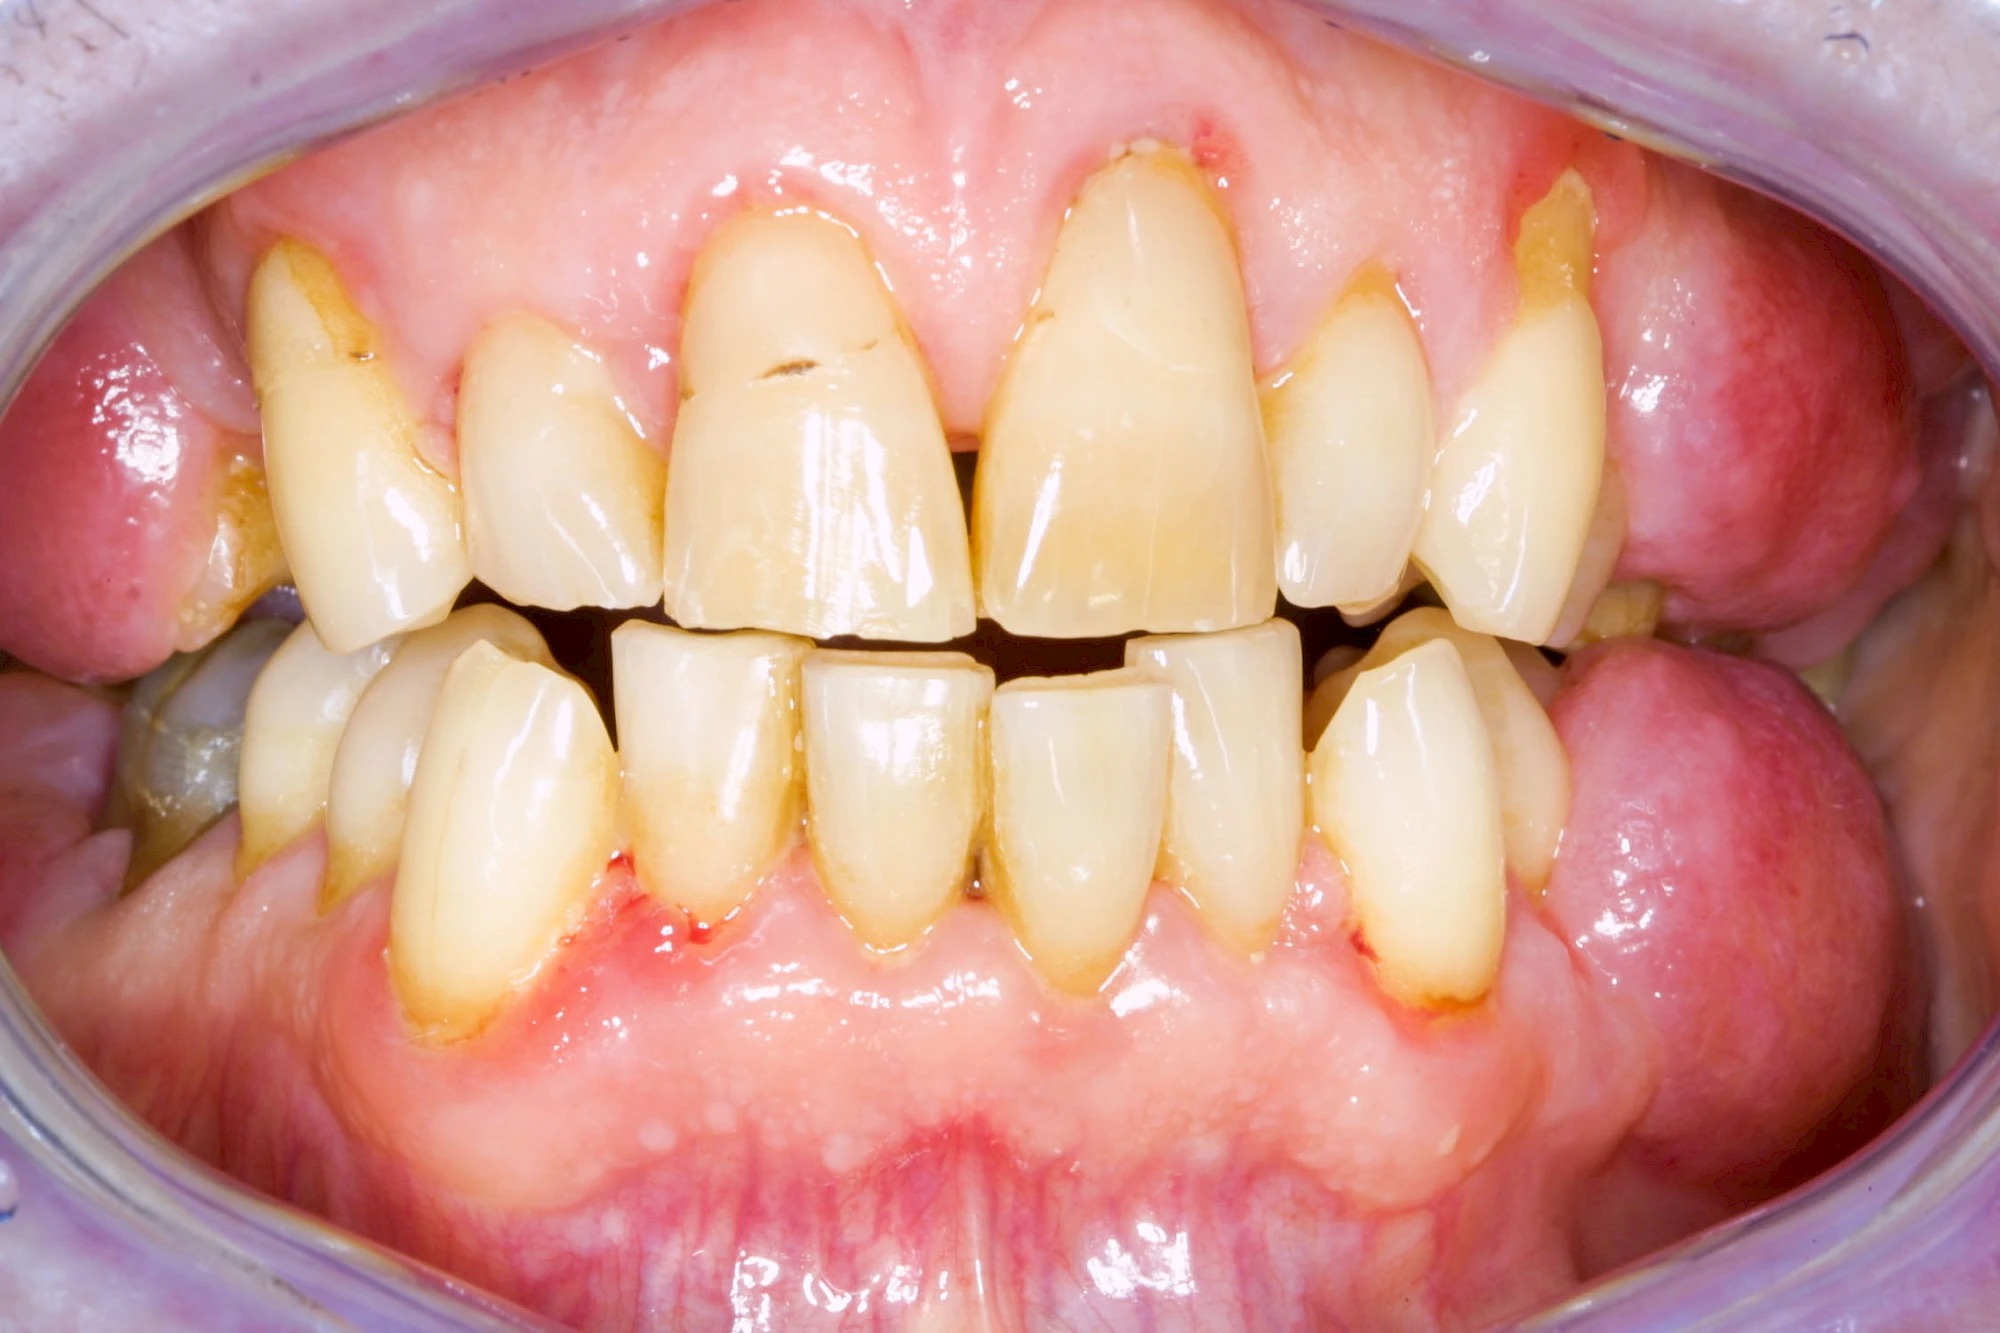

Ist zunächst nur das Zahnfleisch von der Entzündung betroffen, spricht man von Gingivitis. Später, wenn auch der Knochen um die Zähne herum entzündet ist, spricht man von einer Parodontitis. Bei der Parodontitis wird der Knochen nach und nach abgebaut und das Zahnfleisch zieht sich zurück. Die Zahnhälse und Zahnwurzeloberflächen liegen mehr und mehr frei. Die Zähne werden zunehmend lockerer und fallen schließlich aus.

Gingivitis & Parodontitis: Stadien